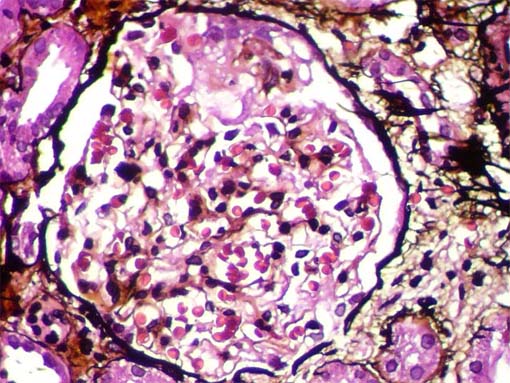

Figure 4.

Methenamine-silver

stain, X400.